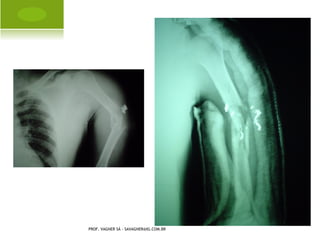

F RATURA - LUXAÇÃO OMBRO

PROF. VAGNER SÁ - SAVAGNER@IG.COM.BR